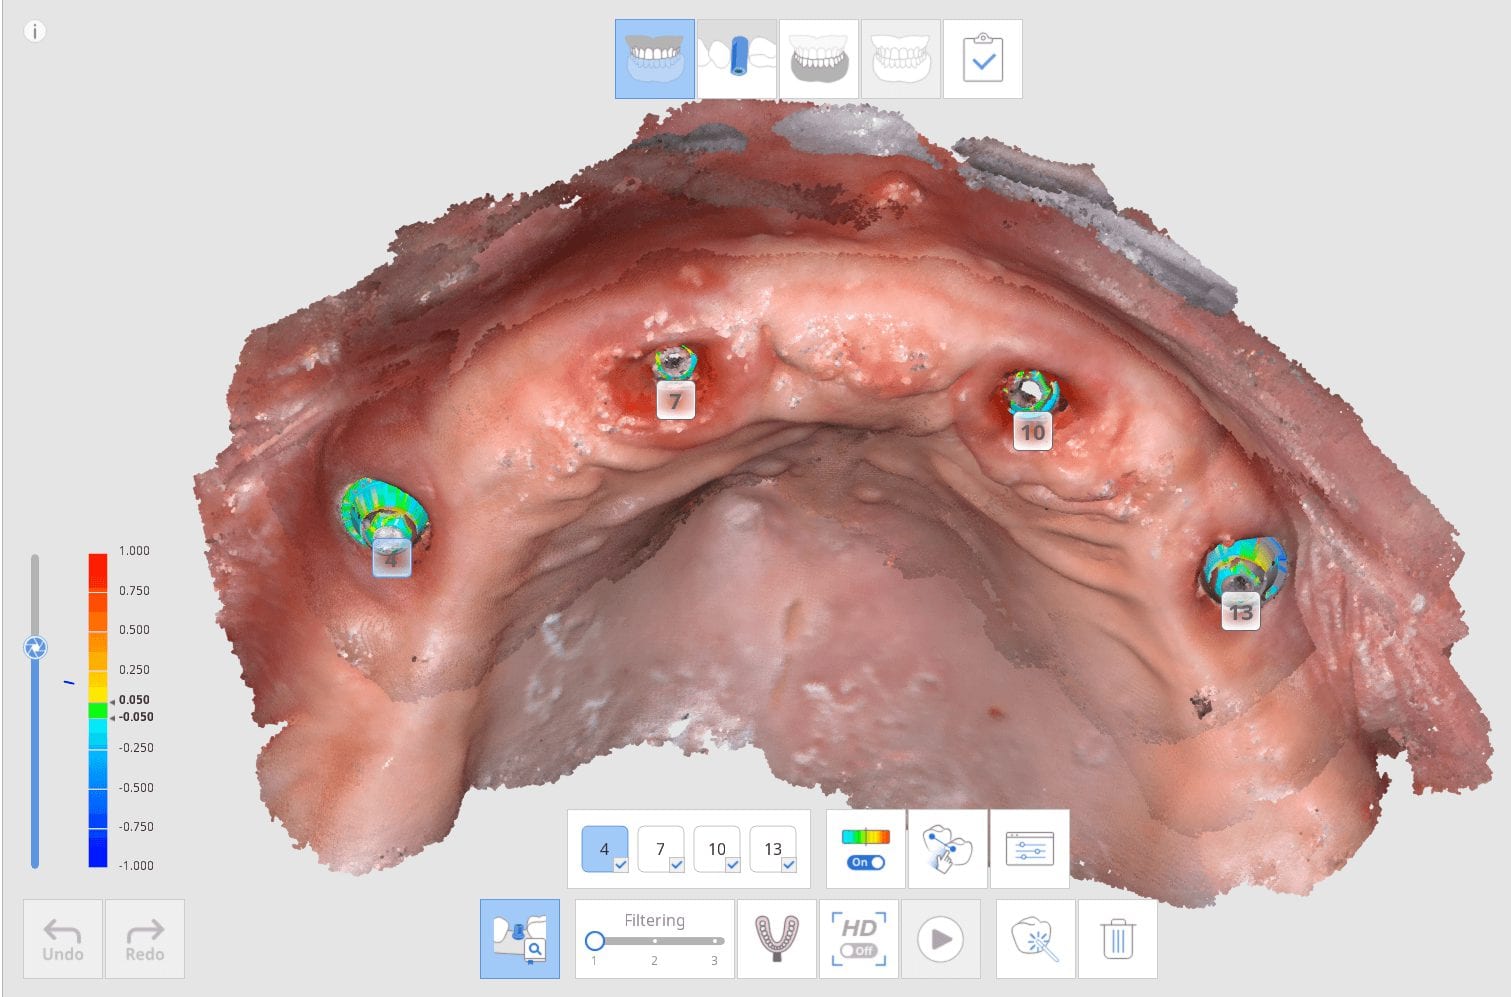

Live Intra-Oral Scan Verification Jigs for Full Arch Scans and Global Accuracy

October 25, 2019This is a detailed video demonstration that shows you how to capture full arch scans for multi unit implant cases in edentulous jaws and, more importantly, how to assess its […]